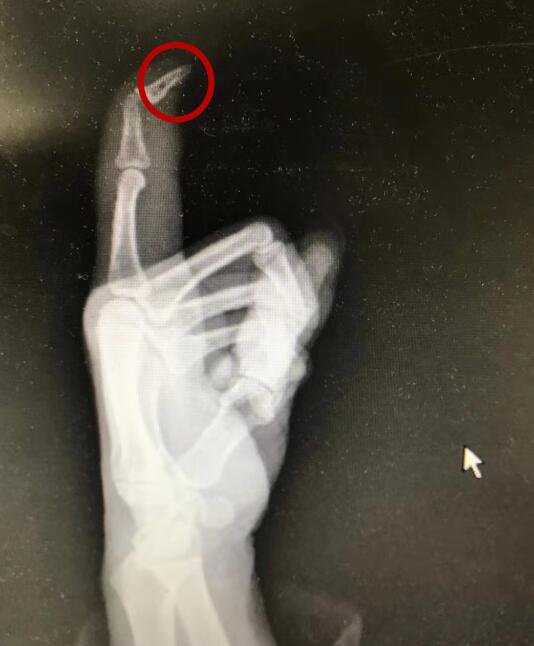

该院接诊的手外科副主任医师吴波介绍,患者右手食指末节触觉丧失,指尖肌肉坏死萎缩并发黑,说明已细菌感染发炎、坏死,现在,病情已发展成“坏疽”,需要通过手术截掉坏死的指尖。吴波告诉记者,他在手外科工作近20年,第一次碰到手指因扎伤导致需截肢的患者,“如果当时患者能及时找到专业医生,切开伤口引流排脓,便不至于变成坏疽。”